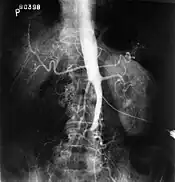

| Plate from Gray's Anatomy showing the abdominal aorta and the common iliac arteries | |

The physical examination usually shows weakened femoral pulses and a reduced ankle-brachial index. The diagnosis can be verified by color duplex scanning, which reveals either a peak systolic velocity ratio ≥2.5 at the site of stenosis and/or a monophasic waveform. MRA and multidetector CTA are often used to determine the extent and type of obstruction. Another technique is digital subtraction angiography which allows verification of the diagnosis and endovascular treatment in a single session.[1]

Angiography provides important information regarding the perfusion and patency of distal arteries (e.g. femoral artery). The presence of collateral arteries in the pelvic and groin area is important in maintaining crucial blood flow and lower limb viability. However, angiography should only be used if symptoms warrant surgical intervention.[1]